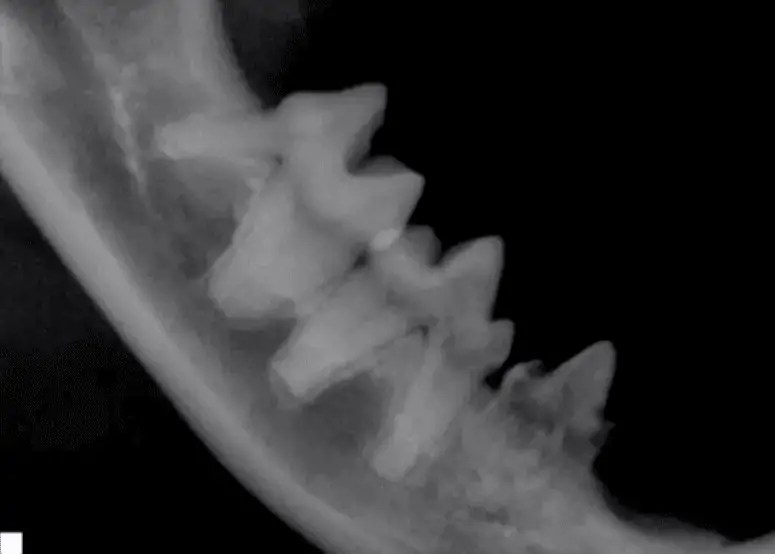

Dental XRay Positioning Guide Feline Mandibular Molars and Premolars Cat Dental X Ray Berg says that it used to be really hard to take dental radiographs in cats, but digital radiography has made it much easier. If extractions are needed, costs can exceed $1,000. Loudoun cat care offers top quality medical, dental and surgical care to cats. Dental radiographs are absolutely critical for proper dental care in feline patients due to the potential. Cat Dental X Ray.

From davidxray.com